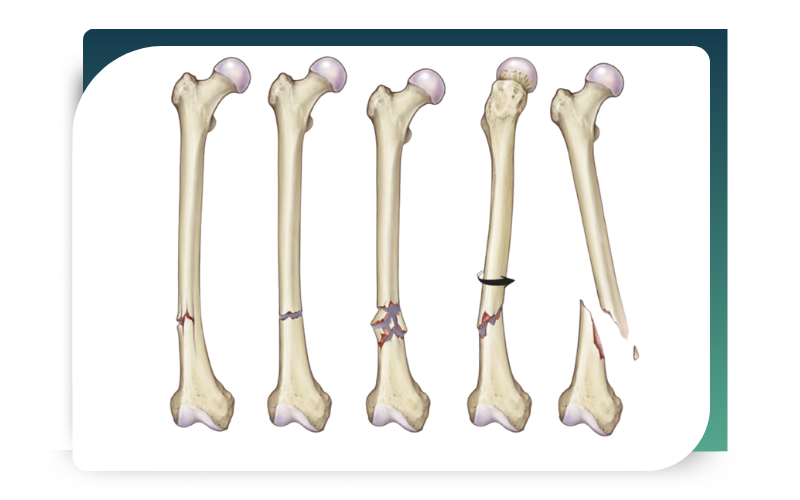

Types of Fractures Treated

Dr. Abhishek Bhalotia specializes in managing a wide range of fractures and traumatic injuries. With extensive clinical experience and advanced orthopedic expertise, he provides comprehensive care for both minor and complex injury cases. In particular, his areas of specialization include:

Simple and complex fractures, which require precise assessment and stabilization

Open (compound) fractures, where immediate and careful surgical intervention becomes essential

Comminuted fractures, involving multiple bone fragments that demand advanced fixation techniques